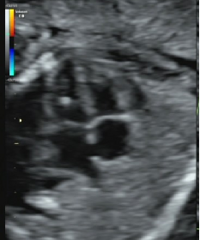

【孕期超声科普】这些常见的孕期超声软指标您了解吗

阅读:1904